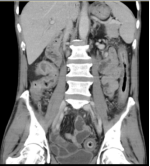

该患者入院时溃疡性结肠炎诊断明确,查血提示WBC16000/ml、HGB130g/L 、CRP29mg/L、ESR44mm/h、TP61g/L、ALB27g/L、pre-ALB120g/L。查ANA、ANCA、结核、EB、CMV(-)。肠镜提示患者全结肠粘膜连续性病变、弥漫性溃疡、粘膜充血水肿并覆白色脓液,结肠袋消失。CT提示全结肠弥漫性水肿、增厚,肠管僵硬。分析该患者溃疡性结肠反复发作、逐渐加重,并且应用美沙拉嗪、激素、免疫抑制剂及单抗治疗效果不佳,所以有全结肠切除的指征。但患者近3月内应用过类克及激素治疗,此时进行手术,势必会出现术后吻合口瘘、腹腔感染等严重并发症。

肠镜下肠粘膜表现    CT提示结肠肠管弥漫性病变   切除的结肠标本